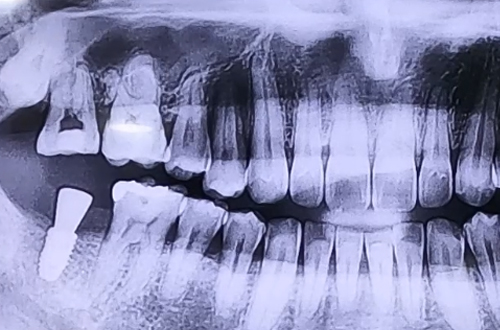

BEFORE

기존에 임플란트를 받던 치과가 문을 닫게 되어 치료가 중단된 것과 작은 어금니의 통증으로 내원해 주신 환자분이십니다.

본원에서는 다양한 종류의 임플란트를 취급하고 있기 때문에 어떤 임플란트를 사용했든 중단된 치료를 이어서 마무리할 수 있어 꼭 맞는 보철을 제작하여 마무리를 해 드렸습니다.

통증을 호소하신 어금니는 염증으로 인해 잇몸이 많이 약해져 있었으므로 발치 후 염증을 먼저 치료하는 기간을 가진 위 임플란트를 진행하는 지연 식립을 결정하였습니다.

잇몸이 충분히 단단해진 뒤 뼈이식과 함께 골유착에 용이한 임플란트를 선택하여 진행했어요.